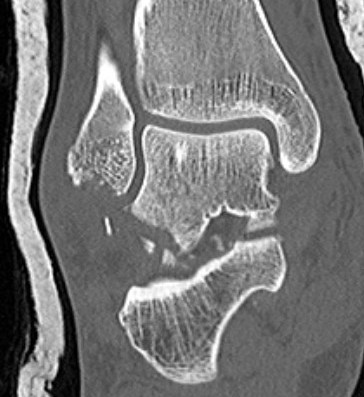

Congruent reduction

Posterior process fracture talus after medial subtalar dislocation